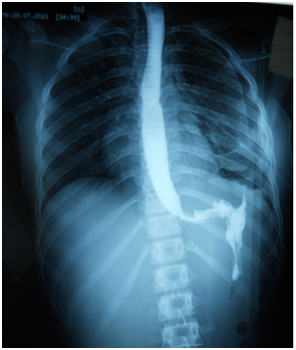

A 17-year-old girl (170cm, 60kg) presented to the emergency department with dyspnea and chest pain after a penetrating stab wound to the chest in the left sixth intercostal space mid-clavicular line, which happened 2hours earlier. Upon physical examination, Pulse was 96 beats per minute and blood pressure was 110/70mmHg, diminished air entry was noticed on the left side of chest. Chest x-ray revealed left hydropneumothorax. Tube thoracostomy was performed left intercostals tube was inserted for drainage. Post-insertion chest x-ray revealed no improvement in the picture of air fluid level (Figure 1) (Figure 2) which was further evaluated by CT that showed fluid collection posteriorly and air anteriorly (Figure 3) (Figure 4). Two days later patient had fever with vomiting and leucocytosis. The nature of the drain from the intercostal tube becomes serosangenous and less hemorrhagic with change in color associated with food. Methylene blue dye (1% concentration) taken orally by the patient was detected in the drain of the intercostal tube two minutes after ingestion (Figure 5). Oral contrast chest x-ray was done, two shots were taken one on swallowing gastrographin, it showed the esophagus outlined without any leakage (Figure 6A). The other shot taken two minutes after oral administration of gastrographin in trendlenberg position, the contrast outlined a track passing from the fundus of the stomach to the left pleural cavity and to the intercostals tube (Figures 6B) (Figure 6C). Laparotomy was performed via midline incision and findings were confirmed. It showed a 3cm orifice of the left copula of the diaphragm with a tear in the gastric fundus which was closed in two layers and the diaphragmatic tear was closed directly with continuous sutures. Two weeks later patient complicated by left empyema with thickened pleura. Thoracotomy was done for complete evacuation of pus and decortication. The patient fully recovered and was discharged 8days after thoracotomy.

Figure 1 Post intercostals tube insertion chest X-ray.

Figure 2 Second day post intercostals tube insertion chest X-ray.